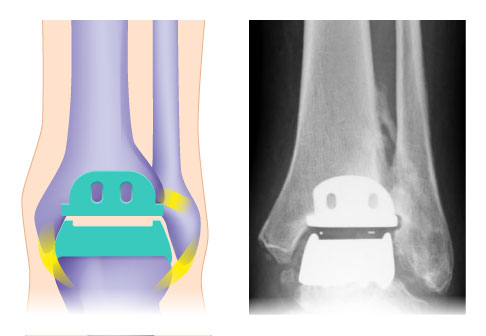

Individualisierte TEP (Totalendoprothese) mit 3 Komponenten:

- gerundete Kappe für die Sprungbeinrolle

- Platte für die Schienbeingelenkfläche

- frei beweglicher Polyethylen-Gleitkern

Der Unterschied zwischen Zwei- und Drei-Komponenten-Prothesen

Die Drei-Komponenten-Prothese ist im Vergleich zur Zwei-Komponenten-Prothese flexibler. Sie unterstützt die natürliche Biomechanik des Sprunggelenks, weil sie in alle Richtungen beweglich sind. Die Drei-Komponenten-Prothese kann bei stabilen und korrekten Achsverhältnissen knochensparend eingesetzt werden.

Bei den individualisierten TEP (Totalendoprothesen) für das Sprunggelenk werden sowohl das Sprungbein (Talus) als auch die Schienbeingelenkfläche (Tibiagelenkfläche) mit einer Metallkappe überzogen. Die Rückflächen der Kappen sind titanbestrahlt und mit Hydroxylapatit beschichtet und gehen während des Heilungsprozesses eine stabilen Verbindung mit dem natürliche Knochen ein.

Die dritte Komponente der Prothese ist ein frei beweglicher Polyethylen-Gleitkern, der die wichtige Bewegung zwischen den beiden Gelenkpartnern vermittelt. Die freie Beweglichkeit des Gleitkernes ermöglicht eine uneingeschränkte Belastung der Prothesenflächen. Die Kunststoffkerne wurden in den letzten Jahren optimiert. Sie sind härter und bewirken eine bessere Quervernetzung des Polyethylens.